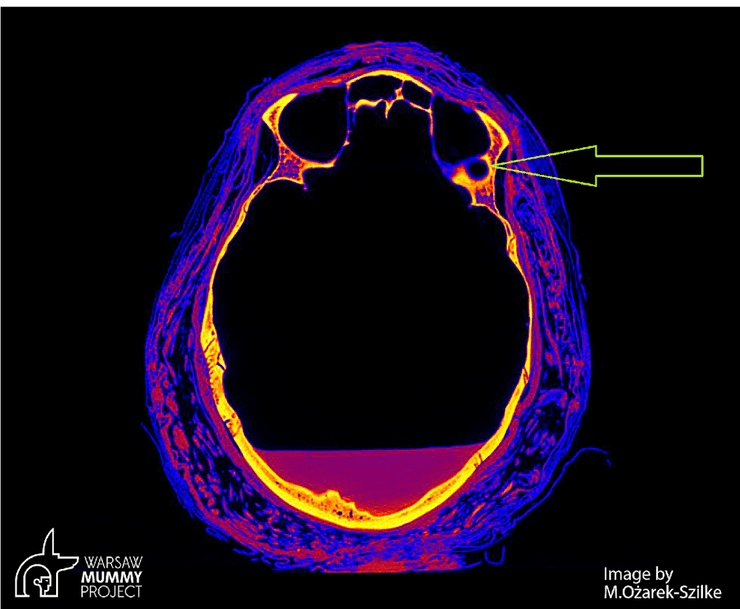

череп, зміна в черепі, пухлина, фото

Жовта стрілка вказує на зміну, спричинену пухлиною

Згідно з новим дослідженням учених із Варшави, легендарна вагітна єгипетська мумія віком 2000 років померла від рідкісної форми раку. Експерти проводили сканування черепа стародавніх останків, коли виявили незвичайні мітки на кістці, пише The First News.

Вони дійшли висновку, що мумія, найімовірніше, померла від рідкісного типу раку — раку носогорла. Зображення, опубліковані вченими, показують череп із пошкодженнями, спричиненими пухлиною.

"Під час дослідження черепа ми помітили великі дефекти в частинах кісток. Ці дефекти були більшими, ніж ті, які зазвичай утворюються під час муміфікації", — розповіла вчена Маржена Ожарек-Сілке.

"По-перше, ми спостерігаємо незвичайні зміни в кістках носогорла, які не типові для процесу муміфікації. По-друге, висновки рентгенологів на основі комп'ютерної томографії вказують на можливість змін у кістках, спричинених пухлиною. І по-третє, молодий вік мумії та відсутність іншої причини смерті вказують на онкологічну причину", — зазначив професор кафедри онкології Варшавського медичного університету Рафал Штек.